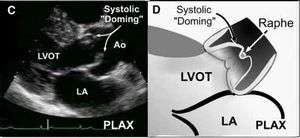

- Minimal excursion of the aortic valve leaflet

- Systolic "doming" on parasternal long

- Raphe in bicuspid aortic valve in diastole may false negatively appear like trileaflet valve

- Only comment on the number of leaflets in systole in parasternal short axis

Systolic "doming"